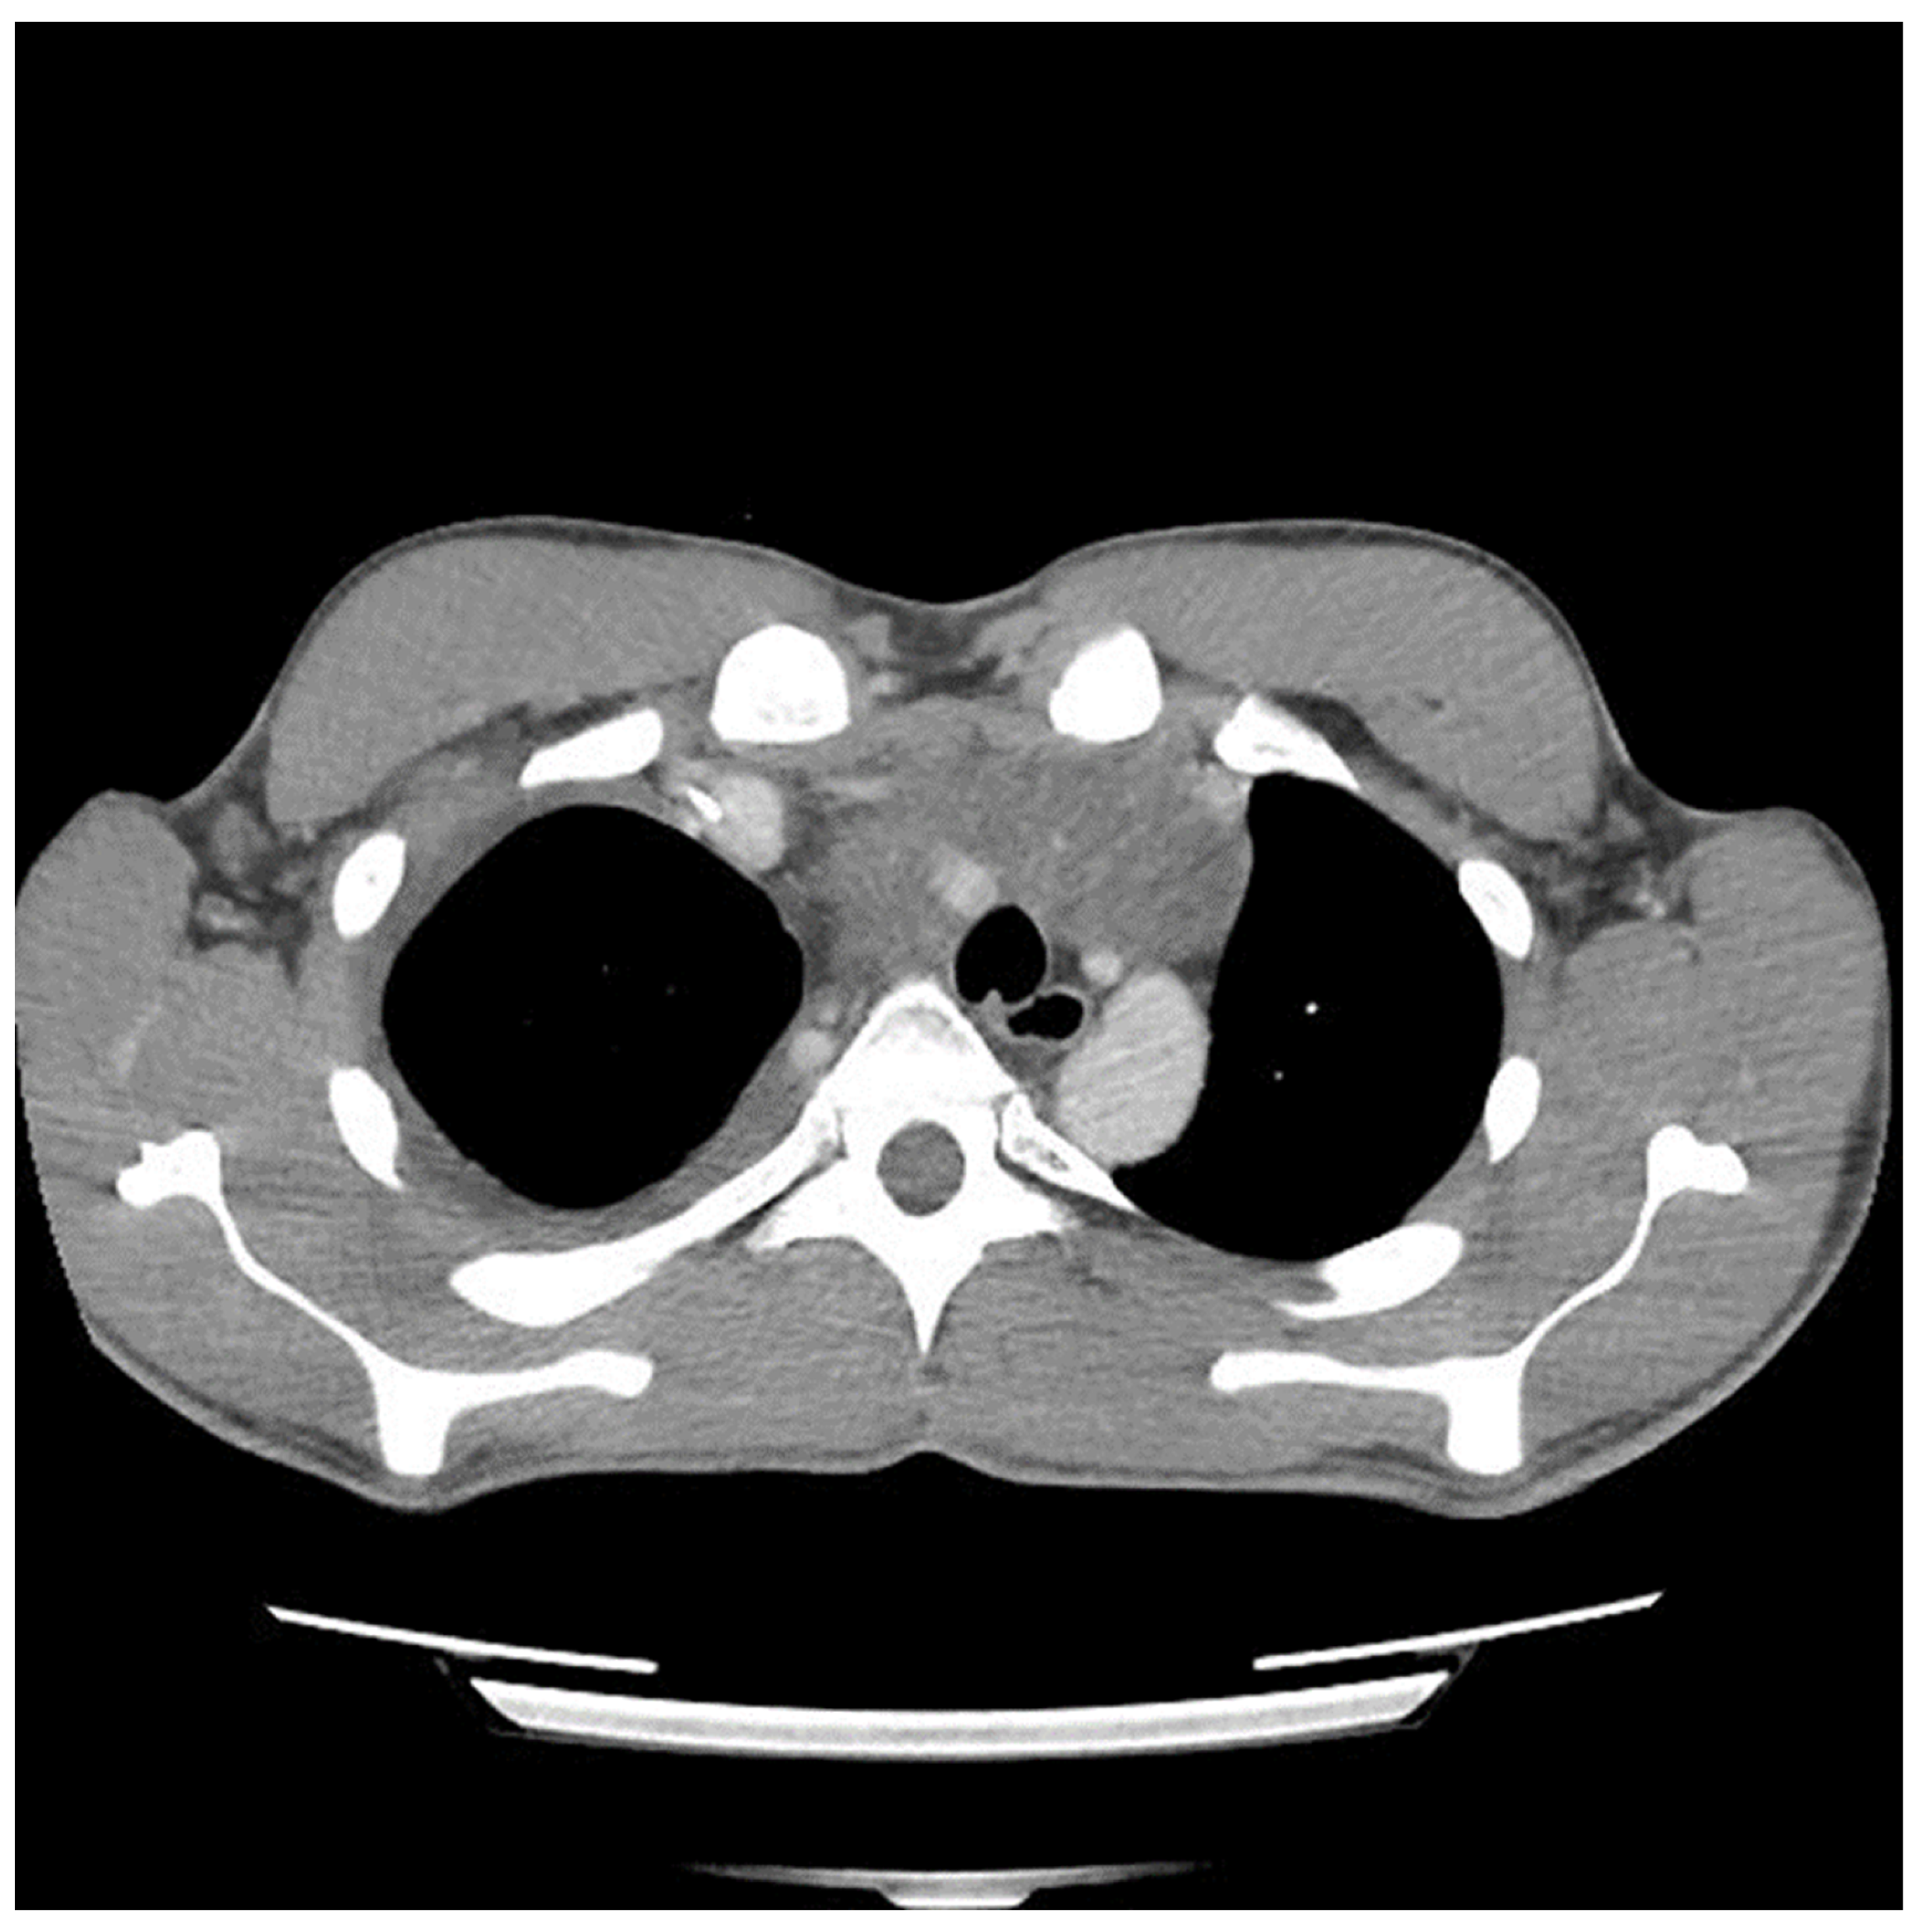

Etoposide, ifosfamide and cisplatin (VIP) chemotherapy was initiated. Bleomycin was not used to avoid pulmonary toxicity, anticipating surgical resection. After the first and second VIP cycles, AFP levels decreased to 1326.96 ng/mL and 219.57 ng/mL, respectively. However, a scheduled computed tomography (CT) scan showed an enlargement of the mass (Figure 2).

Figure 2.

Computed tomography (CT) scan image of mediastinal mass after two cycles of chemotherapy showing interval growth of tumor despite a biochemical response.

The discrepancy between imaging and biochemical responses was evaluated by the patient’s medical oncology team, along with members of a virtual Canadian GCT Discussion Group via email correspondence. Given that any further potential growth could make him unresectable and that the initial pathology showed a significant component of teratoma, which is not chemotherapy-responsive, the consensus was to proceed with surgical resection. During the discussion period and perioperative work-up period, a third cycle of VIP was completed prior to resection. AFP normalized prior to resection.